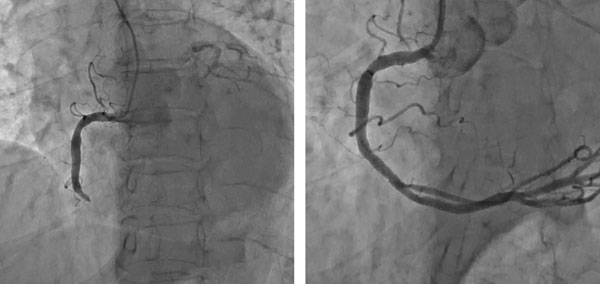

심장은 크게 세 가닥의 관상동맥을 통해 필요한 산소와 영양분을 공급 받는데, 이 관상동맥이란 이름은 세가닥의 동맥이 심장을 관처럼 감싸고 있다고 해서 붙여졌다.

심장에 산소와 영양분을 공급하는 혈관인 관상동맥 혈관벽에 콜레스테롤이 침착되면 죽상반이 생성된다. 그렇게 혈관이 좁아지다가 염증으로 인해 죽상반이 터지고 혈전(피떡)이 생성되면서 혈관이 완전히 막히게 된다. 이렇게 막힌 혈관 때문에 심장 근육(심근)에 혈액공급이 제대로 되지 않으면 심장 조직이 괴사 되는 상황에 이른다. 다시 말해 심근경색은 관상동맥의 내부가 혈전으로 완전히, 또는 부분적으로 막혀 심장 조직이나 근육이 썩는 질환이다.

극심한 가슴 통증이 지속되면 무엇보다 최대한 빨리 관상동맥중재술이 가능한 병원으로 가야 한다. 급성심근경색으로 진단되면 막힌 혈관에 스텐트(금속 그물망)를 넣어 혈전으로 막힌 혈관을 뚫고 다시 피가 흐를 수 있도록 한다. 이렇게 스텐트로 막힌 관상동맥혈관을 뚫는 것을 관상동맥중재술이라고 한다.

과거에는 심근경색증을 치료하기 위해 혈전 용해제를 많이 사용했다. 하지만 일부 환자에게선 효과가 적고, 고위험 환자에서는 뇌출혈의 위험성이 있으며, 혈전이 뚫리더라도 시간이 많이 걸려 치료 효과가 떨어졌다. 최근엔 말초 혈관을 통한 시술인 관상동맥중재술(스텐트 삽입술)을 주로 시행한다.